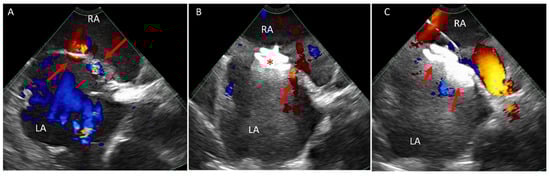

5.2. Transcatheter Tricuspid (Right Atrioventricular) Valve in Valve or Valve in Ring Replacement (TVIV/TVIR)